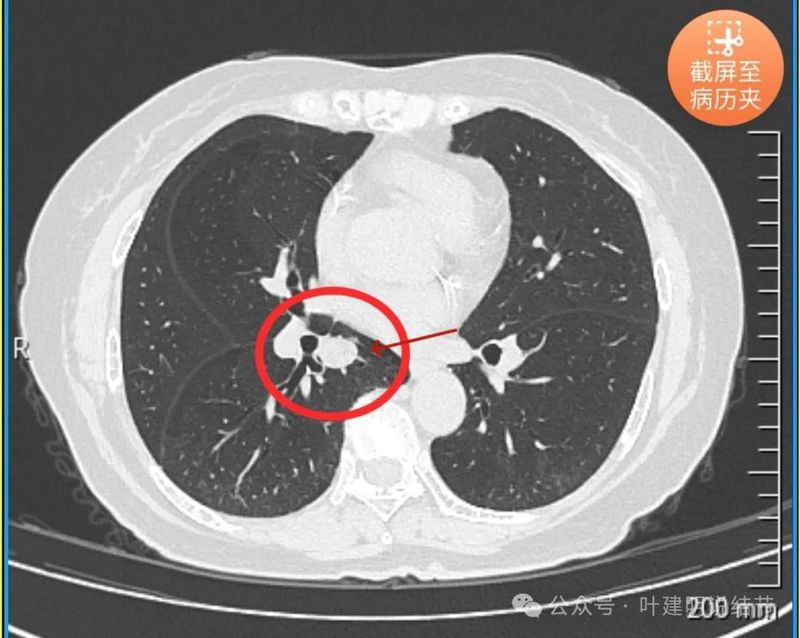

再看2024年5月时复查的影像:

分叶,混合偏实性密度,血管贴边走行。

与支气管紧贴,黄色箭头所示处似乎支气管壁与病灶已经愈着。

上图又见结节与支气管不是都愈着的,说明侵袭性并不强,病灶表面光滑。

天蓝色箭头所指处是北段支气管与病灶之间,感觉较2月份贴得近了一点点。病灶表面仍是光滑的,总体感觉有膨胀性。